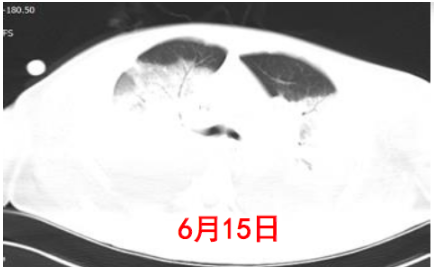

复查患者胸部CT可见肺部病变加重(图5)

图片

5  复查患者胸部CT